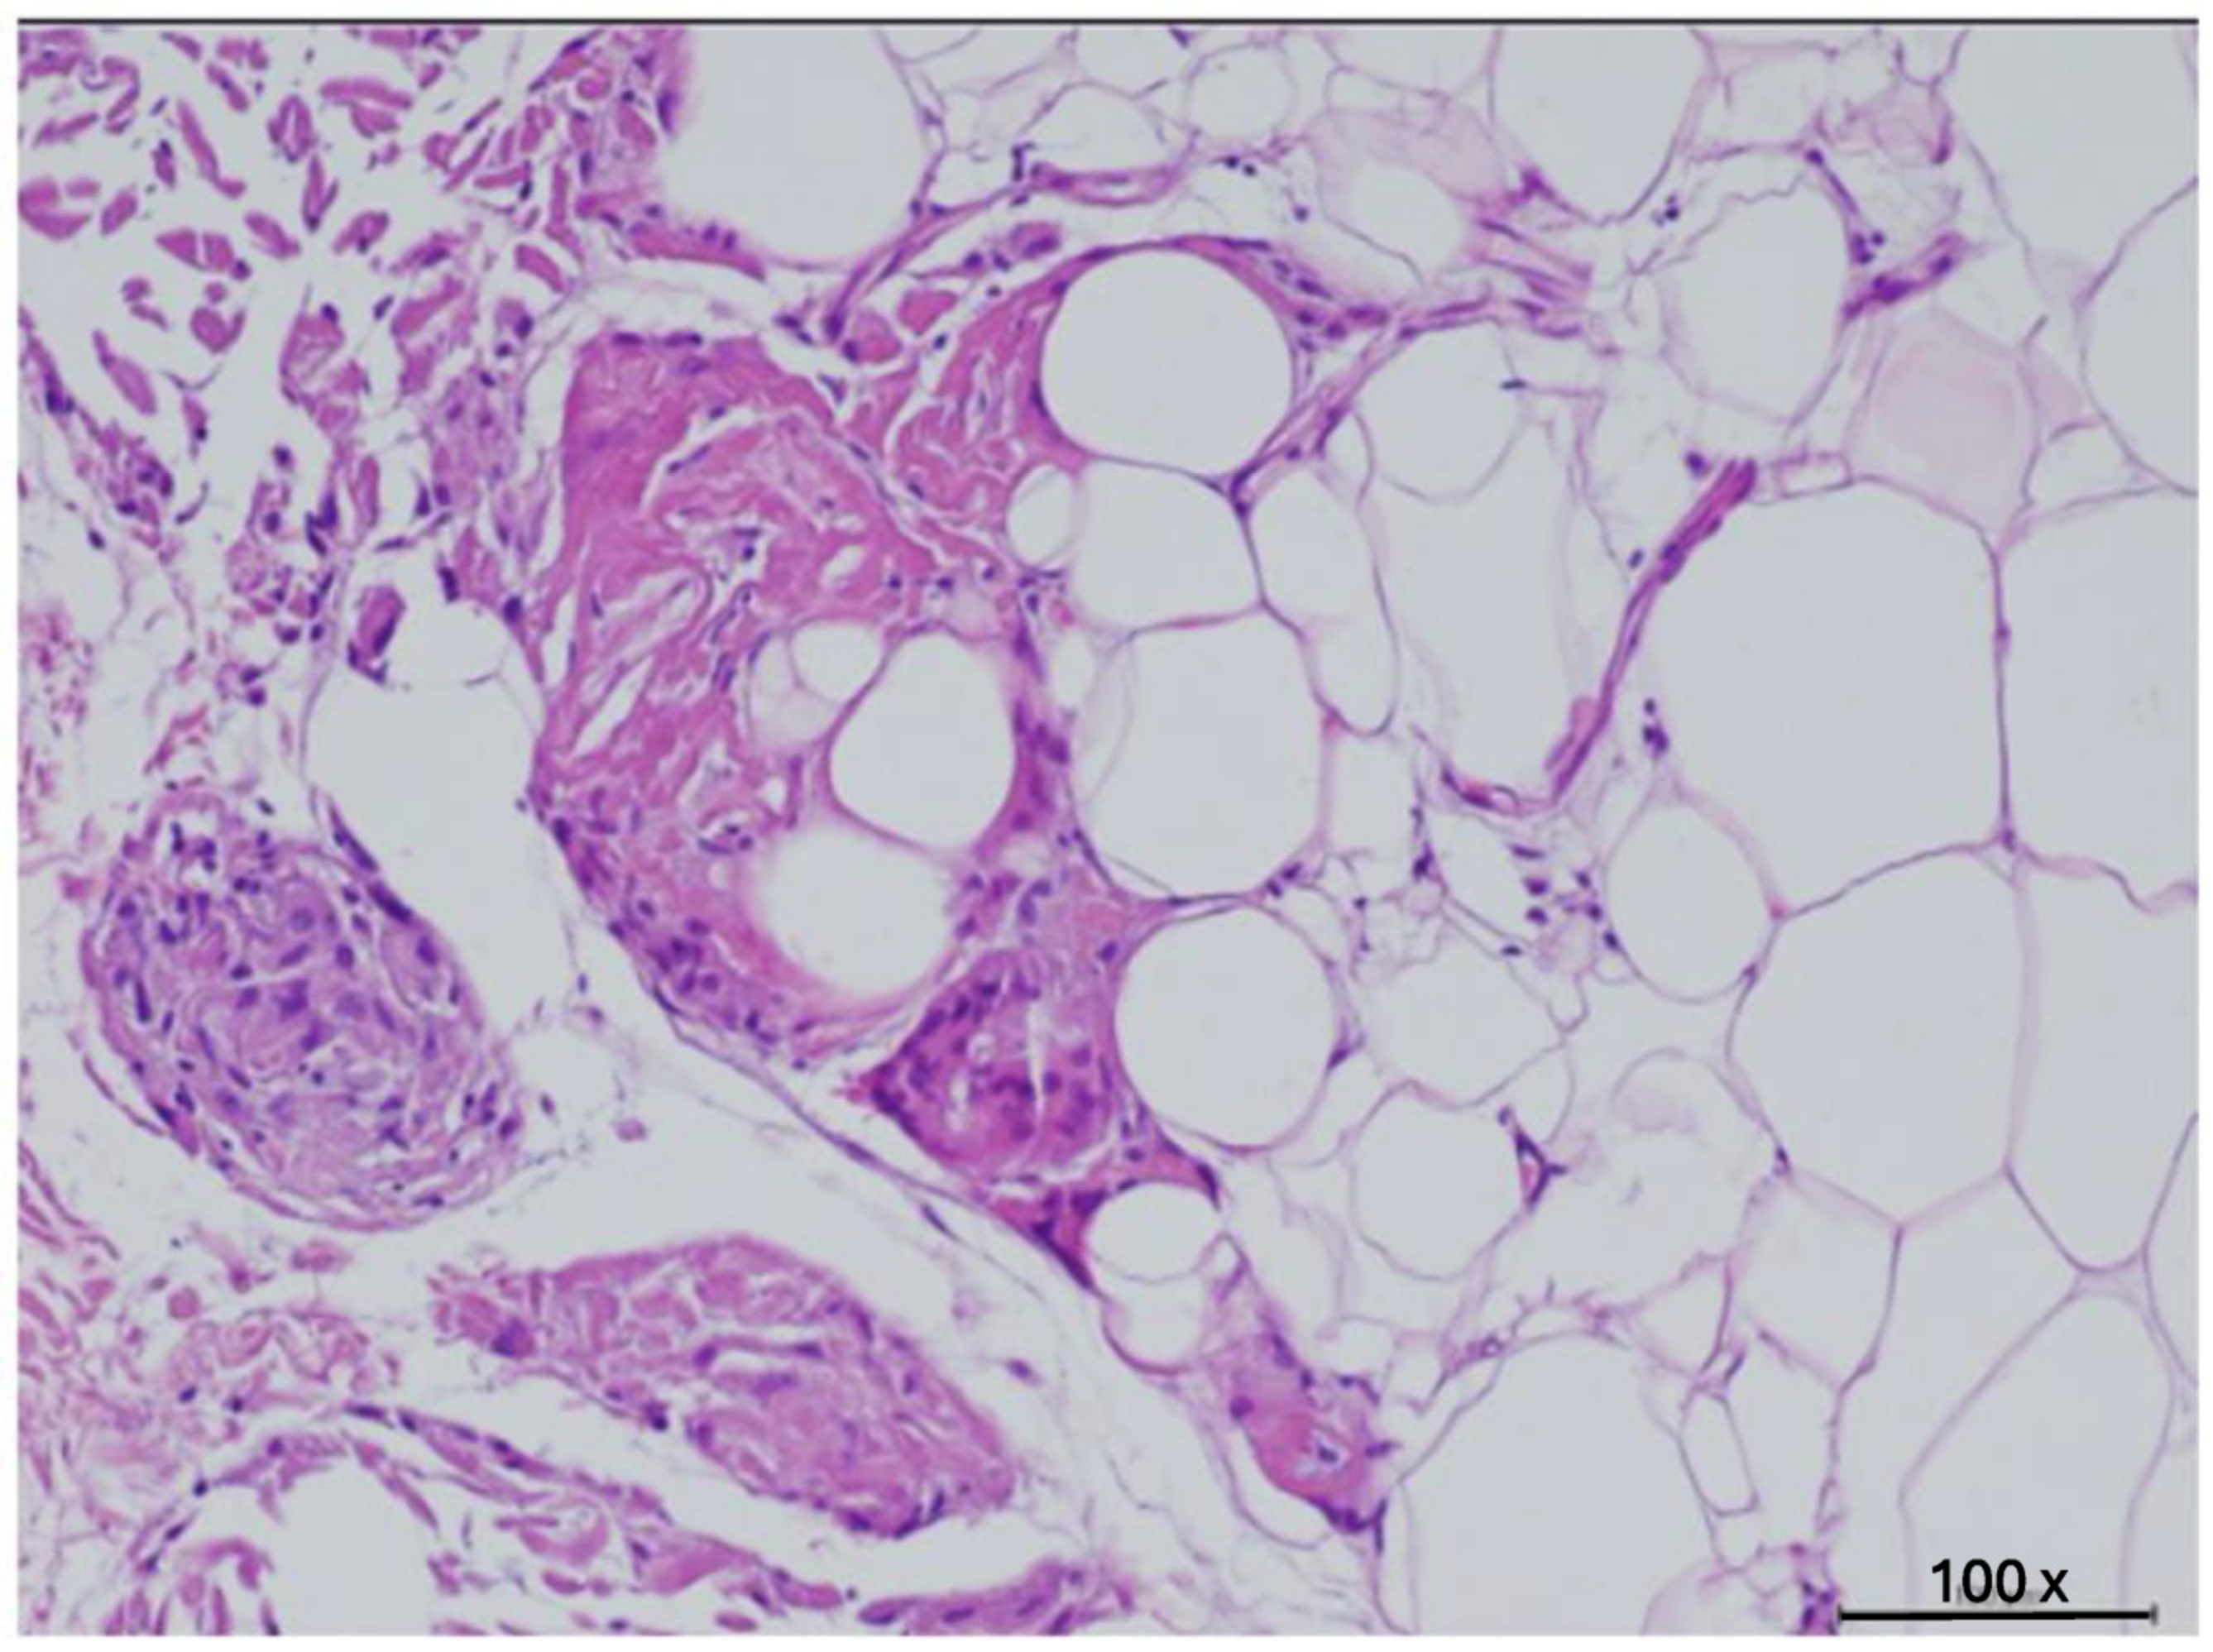

Histology

| Small | (<50 µm) | 10% |

| Medium | (50–69 µm) | 15% |

| Large | (70–89 µm) | 45% |

| Very large | (>90 µm) | 30% |